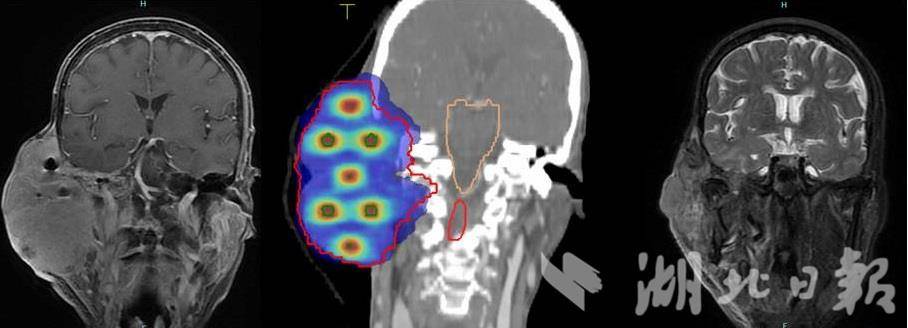

放疗前后影像图(左边为入院时影像,右边为放疗结束后1个月复查影像,中间为晶格放疗剂量分布图)。(受访单位供图)

接诊的头颈部肿瘤放疗二病区主任吴媛团队发现,这颗直径约9.7厘米的巨大肿瘤已经侵犯了李婆婆耳周的软组织、颞骨、腮腺乃至部分神经,属于典型的“难治性”肿瘤。常规的“大范围、均一剂量”放疗模式,很容易伤及周围脆弱的神经和器官,风险极高。

2025年11月,李婆婆先后接受了两个疗程的晶格放疗。奇迹发生了。巨大的肿瘤以肉眼可见的速度开始消退。折磨她多时的剧烈疼痛逐渐减轻,溃烂的创面慢慢愈合,因肿瘤压迫导致的嘴角歪斜也明显改善。一个月后复查,影像显示肿瘤已显著缩小;三个月后,肿瘤基本消退,疗效评估达到了完全缓解。如今,李婆婆的脸上重新看到了轮廓,疼痛消失,只需口服免疫药物维持治疗。